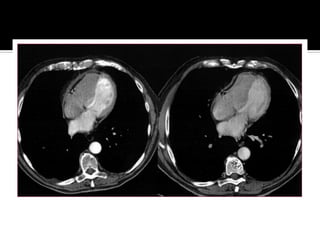

   Panel A. Echocardiographic transmitral flow

pattern with exaggerated respiratory variation in

inflow velocities (>25%).

   Panel B. Transaxial CT image (slice thickness

3.0 mm) of the heart at mid-ventricular level,

demonstrating severe calcification of the

pericardium (arrows). In addition, bilateral pleural

effusion is seen. AO, descending aorta; PE,

pleural effusion.

   Panel C. Three-dimensional volume rendering

technique reconstruction of the whole chest.

Nearly circumferential pericardial calcification is

seen (structures of high CT density, such as bone

and calcification, are rendered in white colour).

   Panel D. Three-dimensional volume rendering

technique reconstruction of the heart. To exclude

the non-calcified part of the heart, a threshold of

130 Hounsfield units (common threshold for

coronary calcification in CT imaging) was chosen.